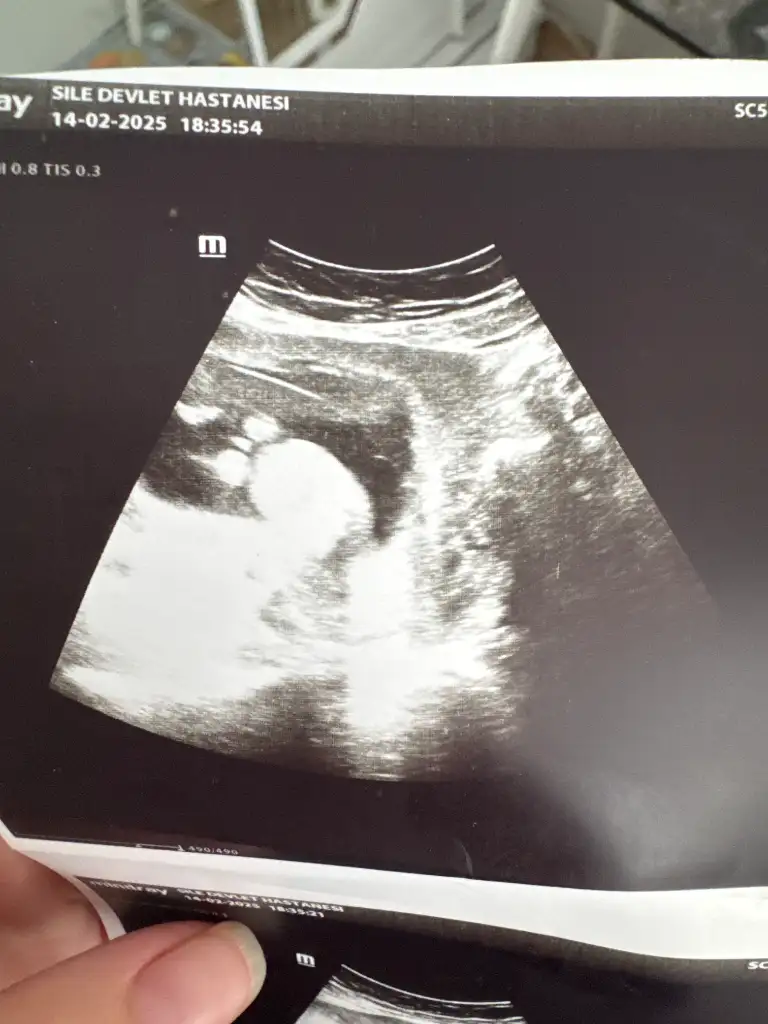

Bende çıkıntı gibi gördüm 19 haftada artık net bişey söylemesi gerekirdi19 haftalık doktor kıza benzetti ama bir cikinti var penise benzetmedim dedi

Benim 12 ve 13 haftalık görüntüye benziyor ama bana da kordon iki bacağının arasında yine de yüzde doksan erkek gibi dedi şu an 16 haftalık haftaya tekrar gidicem15+3 günlük doktor kıza benziyor dedi ama ben erkek görüyorom. Sizce?

13. Haftada da böyle göründü15+3 günlük doktor kıza benziyor dedi ama ben erkek görüyorom. Sizce?

Haber edin lütfen. 3 hafta sonra gel dedi bana. Bekleyelim bakalımBenim 12 ve 13 haftalık görüntüye benziyor ama bana da kordon iki bacağının arasında yine de yüzde doksan erkek gibi dedi şu an 16 haftalık haftaya tekrar gidicem

Foto net diğil. Amma erkek gibi hiss etdim. Sizde 16-haftamı burda?Benim 12 ve 13 haftalık görüntüye benziyor ama bana da kordon iki bacağının arasında yine de yüzde doksan erkek gibi dedi şu an 16 haftalık haftaya tekrar gidicem

Yok şu an yeni 16 hafta oldu. Resimlerdeki 12 ve 13 haftalık görüntüsüFoto net diğil. Amma erkek gibi hiss etdim. Sizde 16-haftamı burda?